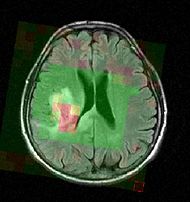

Color-coded MRSI in the localization and grading of brain tumors.

Magnetic resonance spectroscopic imaging (MRSI) is a non-invasive diagnostic method used to determine the relative abundance of specific metabolites at arbitrary locations in vivo. Certain diseases - such as tumors in brain, breast and prostate - can be can be associated with characteristic changes in the metabolic level. Thus, proton MRSI is in principle very well suited for the detection, localization and grading of these diseases. A major challenge in MRSI, however, lies in the post-processing and evaluation of the acquired spectral volumes.